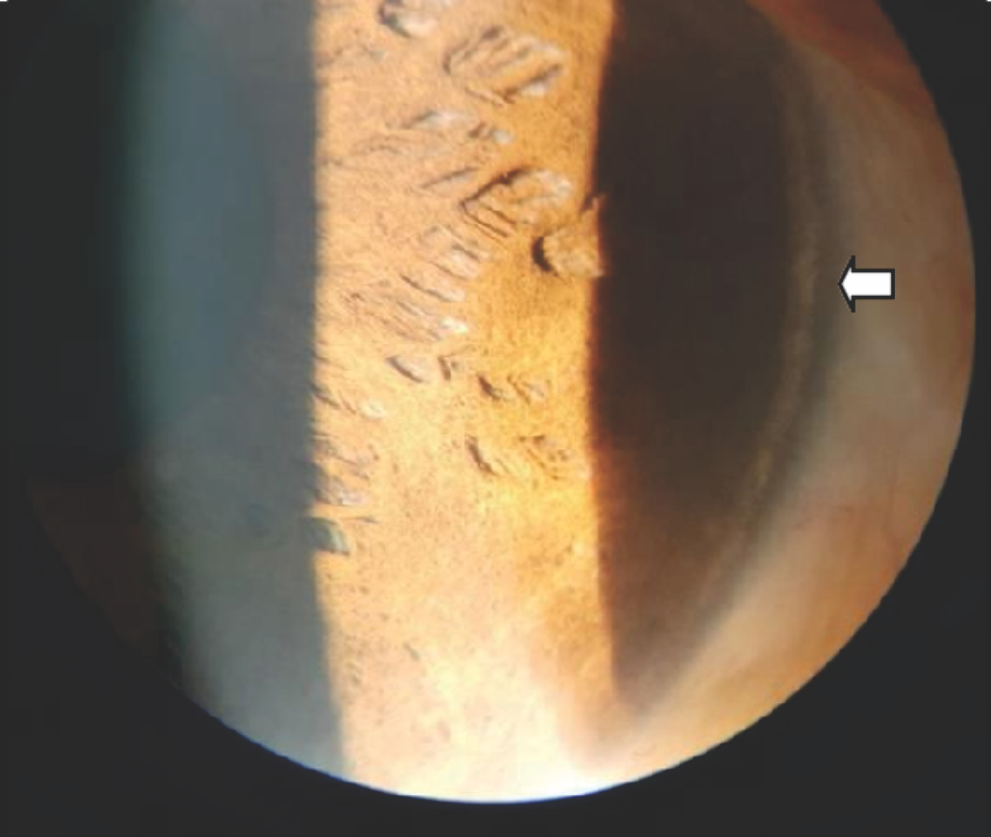

Figure 4: Arrow head showing perilimbal calcific deposit.